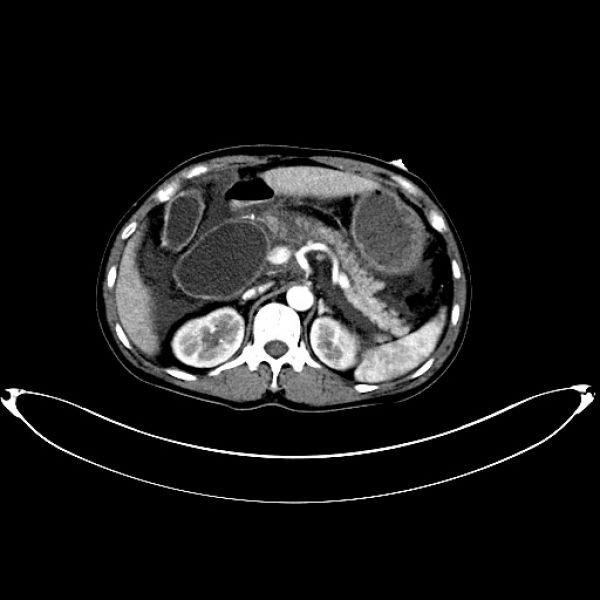

石某某,因突发上腹痛疼痛10小时入院。入院时完善急诊血常规、生化、肝功能、胰代谢以及肝胆脾增强CT等检查,考虑诊断“急性胰腺炎;胰腺假性囊肿”,进一步完善磁共振平扫+MRCP检查,确诊为胆总管囊状扩张症(Ia、C-P型)并发急性胰腺炎。首先进行胰腺炎治疗,予以禁食禁饮、抗炎、护胃、补液、抑制胰腺内外分泌、通便等治疗。经积极治疗,病情稳定后,复查生化相关指标恢复正常,王文儿主任指示:完善术前相关评估,有限期手术指征,无明显手术禁忌,于4月16日在麻醉科及护理工作人员的积极配合下成功完成全腹腔镜下胆总管囊肿剥除+胆囊切除+胆肠内引流术,术中于胆肠吻合口后方放置一18#引流管,术中生命体征平稳,术中失血量约50ml,手术历时约4.5小时,麻醉复苏成功后安返病房。

在诊疗过程中科学的诊疗决策对于患者诊治过程中的顺利推进起到举足轻重的作用。患者因上腹痛10小时入院,完善相关生化以及CT影像检查发现:第一,胰代谢异常明显,结合临床表现和影像学检查,急性胰腺炎诊断明确;第二,上腹部CT发现胰头区有囊性占位,报告:假性囊肿形成可能。王文儿主任仔细阅片以及根据发病特点分析,胰头区囊性占位极似胰腺假性囊肿,根据腹痛特点及胰代谢指标分析,最容易考虑诊断为“急性胰腺炎并假性囊肿形成”。但是,王文儿主任进一步指出:发病时间短,一般不可能在短时间内形成假性囊肿,那么就应该考虑是否还有其他病变?是否考虑胆总管囊状扩张症?那么,就需要进一步完善检查,诊断胆总管囊状扩张症最有价值的方法就是MRCP,于是完善MRCP检查后证实了王文儿主任的推断,最终患者诊断为胆总管囊状扩张症(C-P型)并急性胰腺炎。最后我们的诊疗方案分两步走:第一,积极治疗并发症。第二,待病情稳定后实施腹腔镜胆总管囊肿剥除+胆囊切除+胆肠内引流,以加速康复理念为指导,实现患者快速康复出院,赢得病人的信任。

术前影像图片